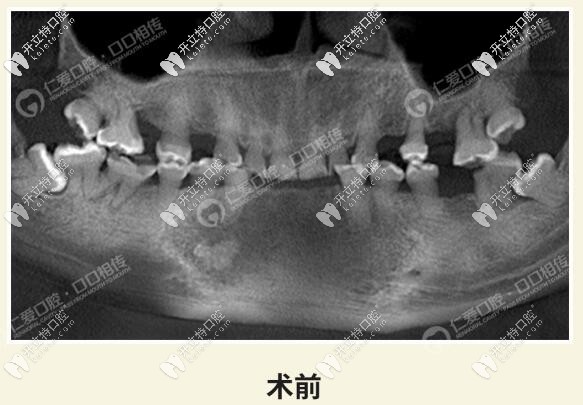

而這位顧客整口牙全牙列均過(guò)度磨耗,經(jīng)過(guò)我院種植醫(yī)生全面檢查分析,判斷咬合垂直距離,采用了全冠修復(fù)。